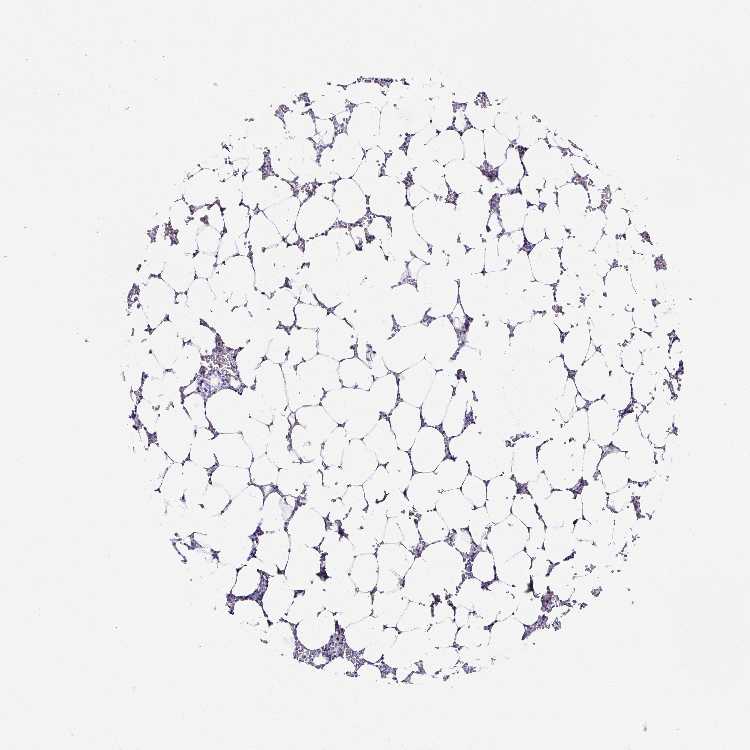

TISSUE PRIMARY DATA BONE MARROW Show tissue menu

Bone marrow

BONE MARROW - Antibody stainingi

Antibody staining in the annotated cell types in the current human tissue is reported as not detected, low, medium, or high, based on conventional immunohistochemistry profiling in selected tissues. This score is based on the combination of the staining intensity and fraction of stained cells.

Each image is clickable and will lead to virtual microscopy that enables deeper exploration of all samples and also displays staining intensity scores, fraction scores and subcellular localization as well as patient and tissue information for each sample.

Antibody HPA053419Antibody HPA054132

Hematopoietic cells Not detectedNot detected